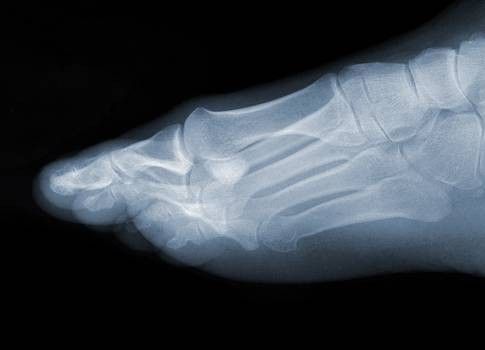

Sintomi della metatarsalgia

Il sintomo più comune della metatarsalgia è il dolore localizzato nella zona metatarsale. Questo, però, può essere accompagnato da ulteriori segnali, quali:

I sintomi della metatarsalgia possono manifestarsi rapidamente o avere un decorso più lungo, sviluppandosi gradualmente. Inoltre, è comunemente riferito dai pazienti che il dolore peggiora quando si sta in piedi, si cammina o si corre soprattutto se scalzi e su una superficie dura, mentre i sintomi tendono ad alleviarsi quando si sta a riposo.